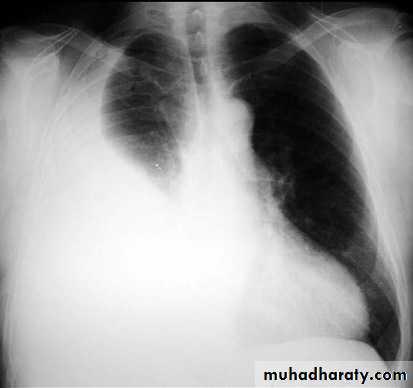

A tension pneumothorax

A tension pneumothorax occurs when intrapleural air accumulates progressively in such a way as to exert positive pressure on mediastinal and intrathoracic structures. It is a life threatening occurrence requiring rapid recognition and treatment is required if cardiorespiratory arrest is to be avoided.Radiographic features

A pneumothorax will have the same features as a run-of-the-mill pneumothorax with a number of additional features, helpful in identifying tension. These additional signs indicate over expansion of the hemithorax:

ipsilateral increased intercostal spaces

shift of the mediastinum to the contralateral side

depression of the HYPERLINK "http://radiopaedia.org/articles/diaphragm" hemidiaphragm